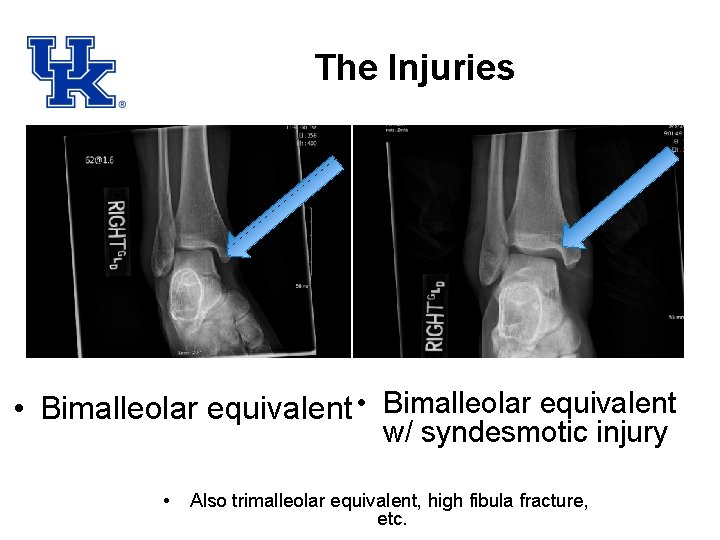

The Injuries • Bimalleolar equivalent w/ syndesmotic injury • Also trimalleolar equivalent, high fibula fracture, etc.